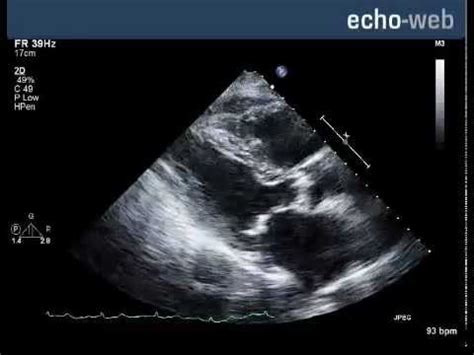

Echo-Web - Severe Aortic Stenosis With Mitral Involvement - YouTube

Echo-Web - Severe Aortic Stenosis with Mitral Involvement - YouTube www.youtube.com

stenosis tricuspid mitral valve aortic echo severe regurgitation doppler web